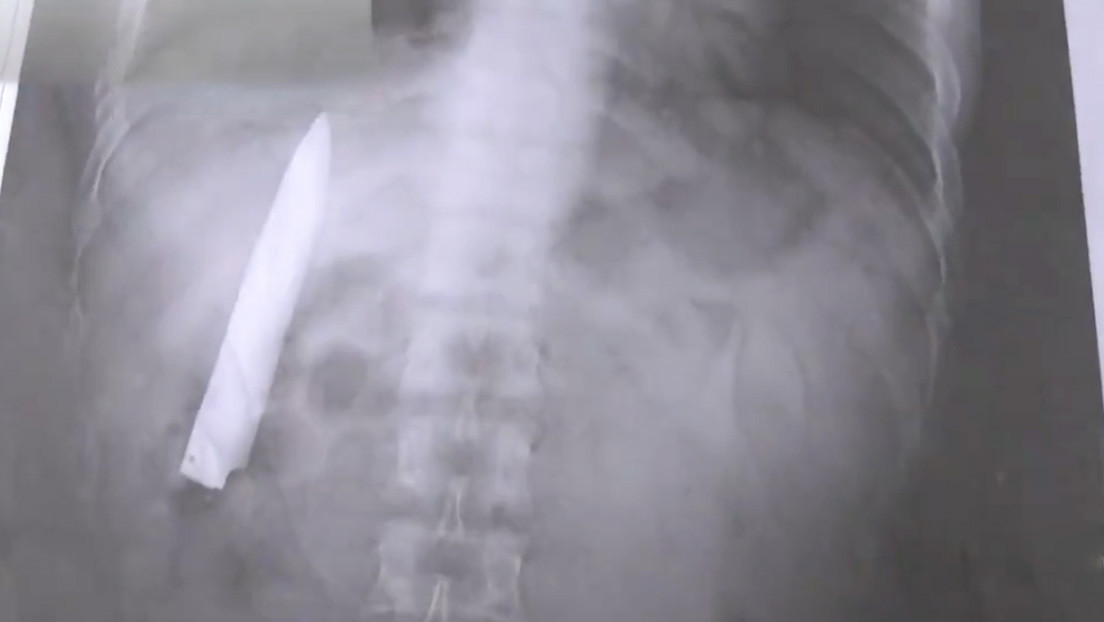

Un hombre descubrió que tenía una hoja de cuchillo dentro de su torso 14 meses después de haber sido apuñalado por un grupo de adolescentes en la ciudad filipina de Kidapawan, señaló el afectado a medios locales el pasado miércoles.

El filipino, de 25 años, se percató de la negligencia cuando asistió el 23 de marzo a un hospital para realizarse pruebas de rayos X, requerimiento para postular a un nuevo trabajo en la provincia de Agusan del Sur.

"Siempre me pregunté por qué siento algo de dolor en mi pecho cuando el clima es frío, pero no tenía idea de que un cuchillo seguía ahí", comentó Tomao.